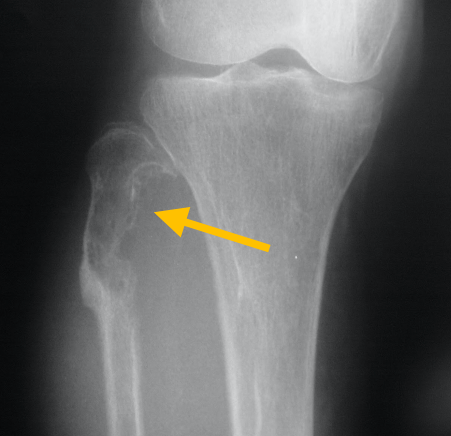

Chondroblastomas are a rare type of noncancerous (benign) bone tumor that begins in is made up of cartilage cells. Chondroblastomas grow at the ends of the body’s long bones (called the epiphysis) near the joints.

Chondroblastomas are a rare type of noncancerous (benign) bone tumor that begins in is made up of cartilage cells. Chondroblastomas grow at the ends of the body’s long bones (called the epiphysis) near the joints.